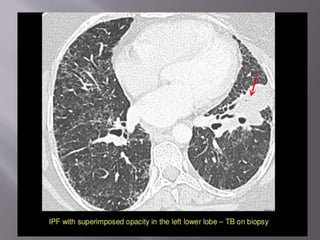

 Patients with IPF have an increased risk of lung

cancer(5X) and tuberculosis; patients who are

receiving corticosteroids are at an increased

risk of opportunistic infection particularly

Pneumocystis jirovecii.

 Patients with IPF and active tuberculosis,

HRCT demonstrated peripheral nodules or

mass-like lesions. Typical patterns of active

tuberculosis, including patchy multifocal

consolidation, tree-in-bud pattern, and

centrilobular nodules, were uncommon.